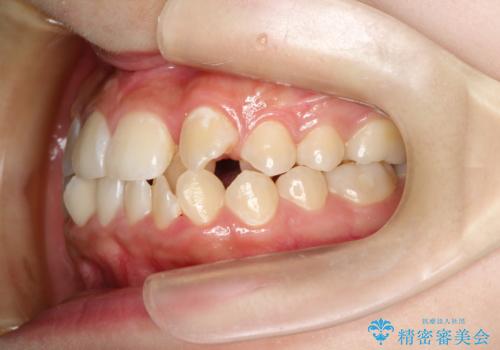

- 上下の前歯に激しい段差がある**重度の叢生(がたつき)**を主訴にご来院されました。精密検査の結果、歯をきれいに並べるためのスペースが圧倒的に不足していたため、上下左右の4番目の歯(第一小臼歯)を計4本抜歯する計画を立案しました。

本症例では、まず抜歯した大きなスペースを効率よく使い、歯の根元から大きく動かす必要があるため、初期段階にワイヤー矯正を採用。その後、細かな噛み合わせの調整や仕上げにインビザラインを使用する「ハイブリッドな矯正治療」で、期間の短縮と精度の高い仕上がりを目指しました。

ワイヤー矯正による先行治療: 最初のステージでは、ワイヤー装置を使用して抜歯したスペースへ歯を大きく移動させました。重度の叢生の場合、ワイヤーを用いることで歯のねじれや大きな移動をスピーディーに行うことができ、治療期間の短縮につながります。